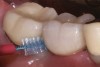

Some amount of microleakage can be expected with any current implant-abutment interface.23,24 External hexagon implants have been found to fail to prevent microleakage.23 Figure 3 and Figure 4 depict an external hexagon implant with an implant-abutment connection vulnerable to microleakage. This same study found internal hexagon implants with internal conical (Morse taper) connection to have the least amount of leakage. Zirconia abutments were found to have more microleakage than titanium abutments. As a result, this study recommended restricting the use of zirconia abutments to cases where esthetic demands are high.23

Fig 3. Clinical and radiographic views of an external hexagon implant restored using a zirconia abutment. The radiograph indicates an implant–abutment connection vulnerable to microleakage. Severe bone loss was due to peri-implantitis.

Figure 3

Fig 4. Clinical and radiographic views of an external hexagon implant restored using a zirconia abutment. The radiograph indicates an implant–abutment connection vulnerable to microleakage. Severe bone loss was due to peri-implantitis.

Figure 4